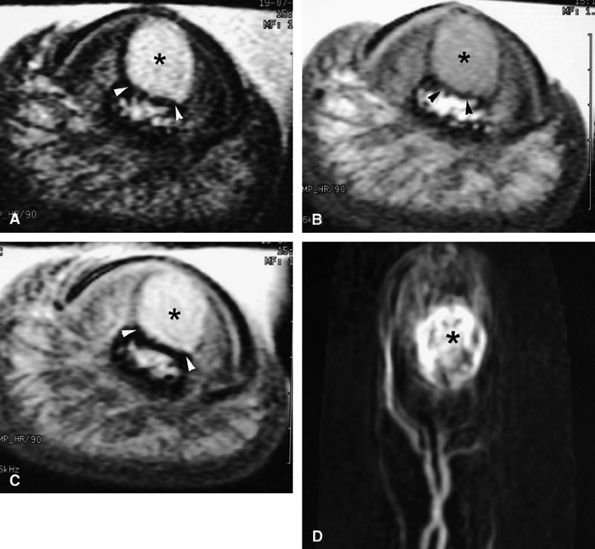

FIGURE 11.9 ● MR of Stener's lesions. MR arthrograms. Coronal (A) and axial (B) T1-weighted fat-suppressed 3D gradient-echo images. The UCL is retracted proximally with a mildly horizontal orientation. The adductor aponeurosis (AA) is partially beneath the UCL. 1 MC, first metacarpal. A more classic Stener's lesion depicted on a coronal proton density-weighted image (C) and a fat-suppressed coronal proton-density weighted image (D), which demonstrate the UCL (arrow) torn from its distal attachment and extending perpendicular to the first ray. The adductor aponeurosis (arrowhead) is seen as a linear structure distal and deep to the torn and retracted UCL.